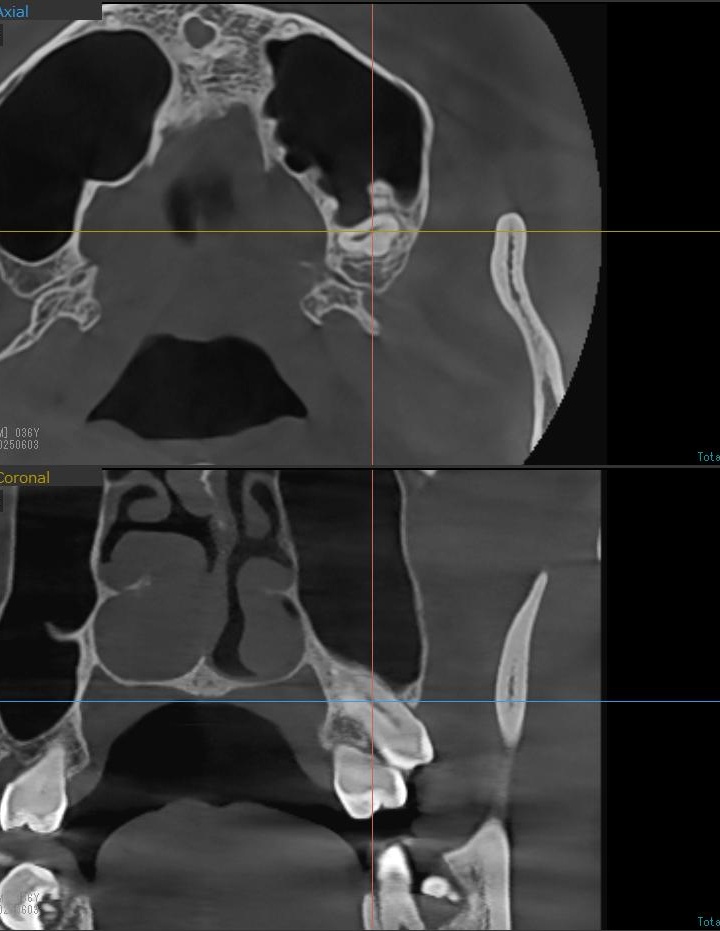

上顎の親知らずの場合、親知らずの根っこが上顎洞という空洞と非常に近い場合もあるため、CT撮影でも確認します。

今回は上顎洞から充分に距離があるため、抜歯は可能と診断されました。